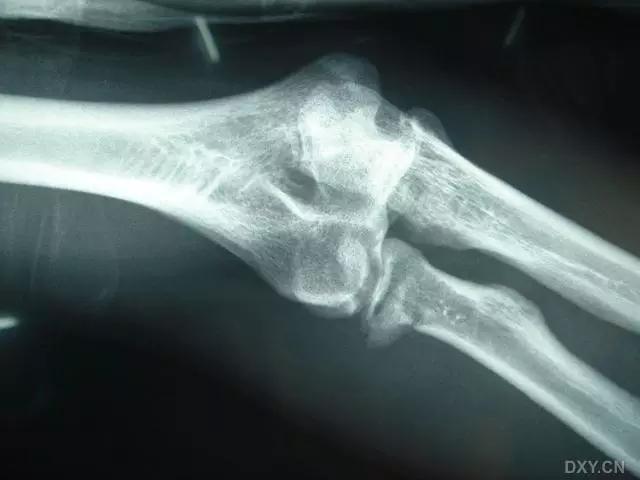

9. Essex-Lopresti 骨折

是桡骨头骨折伴有下尺桡关节脱位,导致骨间膜损伤,桡骨短缩。此种损伤,桡骨头骨折的诊断往往是明确的,容易忽视的是下尺桡关节脱位,特别是早期,下尺桡关节的症状不明显,X 线表示也不明显。

Essex-Lopresti 损伤。前后位(A)和侧位(B)示桡骨头关节内骨折(白色实线箭头);(C~E)伤后 1 个月复诊,患者诉腕关节疼痛,X 线(C,D)发现下尺桡关节脱位,(E)CT 进一步证实损伤的存在 (来源:Radiol Clin North Am. 2015 Jul;53(4):717-36)